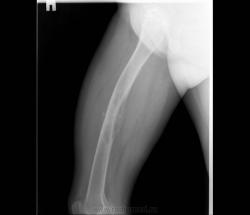

Девочка 9 лет. Родители отмечают, что 2 месяца назад девочка начала предъявлять жалобы на боли в правой пятке. Обследовались, патологии в стопе не нашли. Ребёнок постепенно начал хромать. А несколько дней назад обнаружили припухлость в в/3 бедра. Болей в бедре нет, как ночных, так и дневных. Температура не повышалась. Обратились за помощью - выполнены рентгенограммы, затем - КТ.

Злокачественная опухоль - виден луковичный периостит, инвазивный рост с лизисом кости. Но какая? Вроде бы растет из костного канала. Остеосаркома? Юинг? для этих опухолей структура какая-то больно хрящевая, мягкотканная. Хондросаркома? В таком возрасте? Почему нет клиники злокачественной опухоли кости, прежде всего - болей?

Согласна. Только периостит не луковичный, четкий лизис с козырьками Кодмена-явный признак злокачественности. А насчет болей, действительно в жизни всякое бывает, но, думаю, что ребенок не может отличить их от болей в пятке (!), а прихрамывание может быть и следствием щажения конечности.

+1 за козырек Кодмана.

Коллеги, давайте правильно применять термины. Периостит - окончание воспаления, применяется при остеомиелите. При опухоли - периостоз - окончание избытка, продуктивного процесса. Здесь есть "козырек Кодмена", спикулообразный периостоз, но есть так же луковичный (слоистый) периостоз, который хорошо виден на отдельных КТ-срезах. Другое дело, что для диф. диагноза опухоли (то что процесс агрессивный - сомнений не вызывыает) это, по большому счету, ничего не дает. Однако, обратите внимание на вздутие. Считаю возможны варианты телеангиоэктатической или гигантоклеточной остеосаркомы. Так же не считаю возможным исключить саркому Юинга.

Да, рентгенкартина неоднозначна, конечно, в первую очередь надо исключать зло (Юинга, остеогенную), но не уверена на 100%, что это они, спикул нет, есть луковичный периостит ниже основного очага, но это не критерий злокачественности, вздутие. Был бы возраст помладше, в первую очередь подумала бы о гистиоцитозе или туберкулезе. Еще мысли об аневризмальной кисте и ГКО. Очень хочется узнать результаты гистологии.

При такой протяженности разрушения кортикального слоя и объёме мягкотканого компонента, да и вздутии кости, что здесь может быть кроме Зла? Однако гистология интересна.

Такой вариант тоже возможен, но как мне кажется, менее вероятен. Сама по себе АКК вполне возможна. Но, всё-таки, луковичный периостоз и Кодмена никак, кроме как наличием злокачественности не объяснишь... Слишком уж они явные.

Вот спикулы - это да, злокачественность.